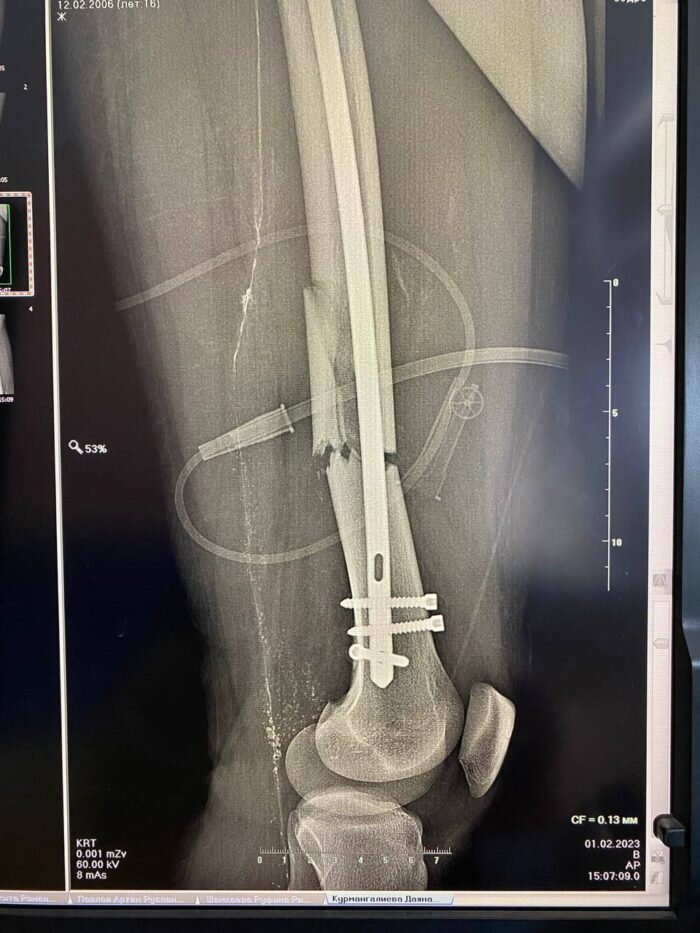

В Оренбурге врачи ОДКБ и четвертой городской больницы провели уникальную операцию на ноге подростка.

Мальчика доставили в Центр детской хирургии с серьезной сочетанной травмой. У подростка был перелом левой бедренной кости со смещением отломков. Сотрудники ОДКБ пригласили на операцию врачей четвёртой городской больницы, которые имеют серьёзный опыт хирургического лечения подобных травм.

Пациенту провели болокираванный интрамедуллярный стержневой остеосинтез. Спустя два дня ребенок смог вставать на костыли. Боль уменьшилась, отек начал спадать. Через неделю подростка надеются выписать из больницы.

Оперировал юного пациента заведующий кафедрой травматологи и ортопедии ОрГМУ, к. м.н., доцент, врач травматолог-ортопед высшей категории Городской Больницы N4 Андрей Гурьянов. Ассистентами выступили травматологи ОДКБ Иван Четвериков и Александр Бугаев.